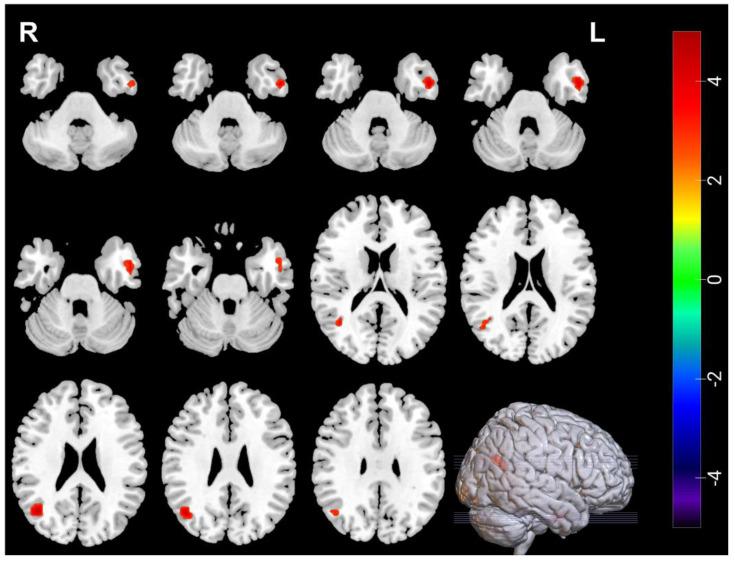

Resting-state functional magnetic resonance imaging (rs-fMRI) was used to investigate the effects of electroconvulsive therapy (ECT) causing brain function changes in adolescents who suffered from depression and suicidal ideation (SI). A total of 30 patients (MDDs) and 25 healthy controls (HCs) matched by gender, age, and education level were enrolled. The amplitude of low-frequency fluctuations (ALFF) and regional homogeneity (ReHo) were used to compare differences between HCs and MDDs at baseline, and differences in ALFF and ReHo pre/post ECT in MDDs. Pearson correlation analysis was used to evaluate the relationship between altered brain function and clinical symptoms. At baseline, MDDs showed decreased ALFF in the left inferior temporal gyrus and right amygdala, decreased ReHo in left inferior temporal gyrus, and increased ReHo in the right inferior frontal gyrus, opercular part and left middle occipital gyrus. After ECT, MDDs showed increased ALFF in the right middle occipital gyrus, decreased ALFF in left temporal pole, left inferior frontal gyrus, opercular part, and right frontal middle gyrus, increased ReHo in the right middle occipital gyrus, and left inferior temporal gyrus. Pearson correlation found HAMD scores at baseline were negatively correlated with ALFF in the left inferior temporal gyrus, and HAMD and BSSI scores after ECT were negatively correlated with ALFF in the right middle occipital gyrus. The abnormal activities of amygdala, inferior temporal gyrus and middle occipital gyrus might be related to depressive and suicidal symptoms in adolescents.

静息态功能磁共振成像(rs-fMRI)被用于研究电休克治疗(ECT)对患有抑郁症和自杀观念(SI)的青少年脑功能变化的影响。共纳入了30例患者(重度抑郁症患者)和25名健康对照者(HCs),他们在性别、年龄和教育水平上相匹配。采用低频振幅(ALFF)和局部一致性(ReHo)来比较HCs和重度抑郁症患者在基线时的差异,以及重度抑郁症患者在ECT治疗前后ALFF和ReHo的差异。采用Pearson相关分析来评估脑功能改变与临床症状之间的关系。在基线时,重度抑郁症患者左侧颞下回和右侧杏仁核的ALFF降低,左侧颞下回的ReHo降低,右侧额下回岛盖部和左侧枕中回的ReHo升高。ECT治疗后,重度抑郁症患者右侧枕中回的ALFF升高,左侧颞极、左侧额下回岛盖部和右侧额中回的ALFF降低,右侧枕中回和左侧颞下回的ReHo升高。Pearson相关分析发现,基线时汉密尔顿抑郁量表(HAMD)评分与左侧颞下回的ALFF呈负相关,ECT治疗后的HAMD和贝克自杀意念量表(BSSI)评分与右侧枕中回的ALFF呈负相关。杏仁核、颞下回和枕中回的异常活动可能与青少年的抑郁和自杀症状有关。